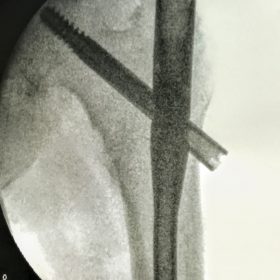

Διατροχαντήριο : Εξωαρθρικό κάταγμα, στην περιοχή ανάμεσα στο ελάσσονα και το μείζονα τροχαντήρα. Αντιμετωπίζεται χειρουργικά με ενδομυελική ήλωση τύπου γ-Nail. Δύο τομές 3 εκατοστών και 1 εκατοστού αντιστοίχως για την εισαγωγή και το κλείδωμα του ήλου μέσα στο οστό. Η μέθοδος είναι κλειστή,σχεδόν αναίμακτη,διάρκειας 30 λεπτών,με τη βοήθεια C-ARM (τηλεόρασης). Στον ασθενή παρέχεται οπτικό υλικό (όλα τα χειρουργικά στάδια) σε CD ή Στικάκι,λόγω της δυνατότητας καταγραφής του χειρουργείου από το C-ARM Ο ασθενής περπατάει άμεσα μετεγχειρητικά στις 5 ώρες μετά την επέμβαση και εξέρχεται από το νοσοκομείο σε 1 -2 ημέρες.

Υποτροχαντήριο :Εξωαρθρικό κάταγμα κάτω από τον ελάσσονα τροχαντήρα του μηριαίου οστού. Αντιμετωπίζεται χειρουργικά με ενδομυελική ήλωση τύπου Long γ-Nail. Δύο τομές 3 εκατοστών και 1 εκατοστού αντιστοίχως για την εισαγωγή και το κλείδωμα του ήλου μέσα στο οστό. Η μέθοδος είναι κλειστή,σχεδόν αναίμακτη,διάρκειας 60 λεπτών,με τη βοήθεια C-ARM (τηλεόρασης). Στον ασθενή παρέχεται οπτικό υλικό (όλα τα χειρουργικά στάδια) σε CD ή Στικάκι,λόγω της δυνατότητας καταγραφής του χειρουργείου από το C-ARM Ο ασθενής περπατάει άμεσα μετεγχειρητικά στις 5 ώρες μετά την επέμβαση και εξέρχεται από το νοσοκομείο σε 1 -2 ημέρες.